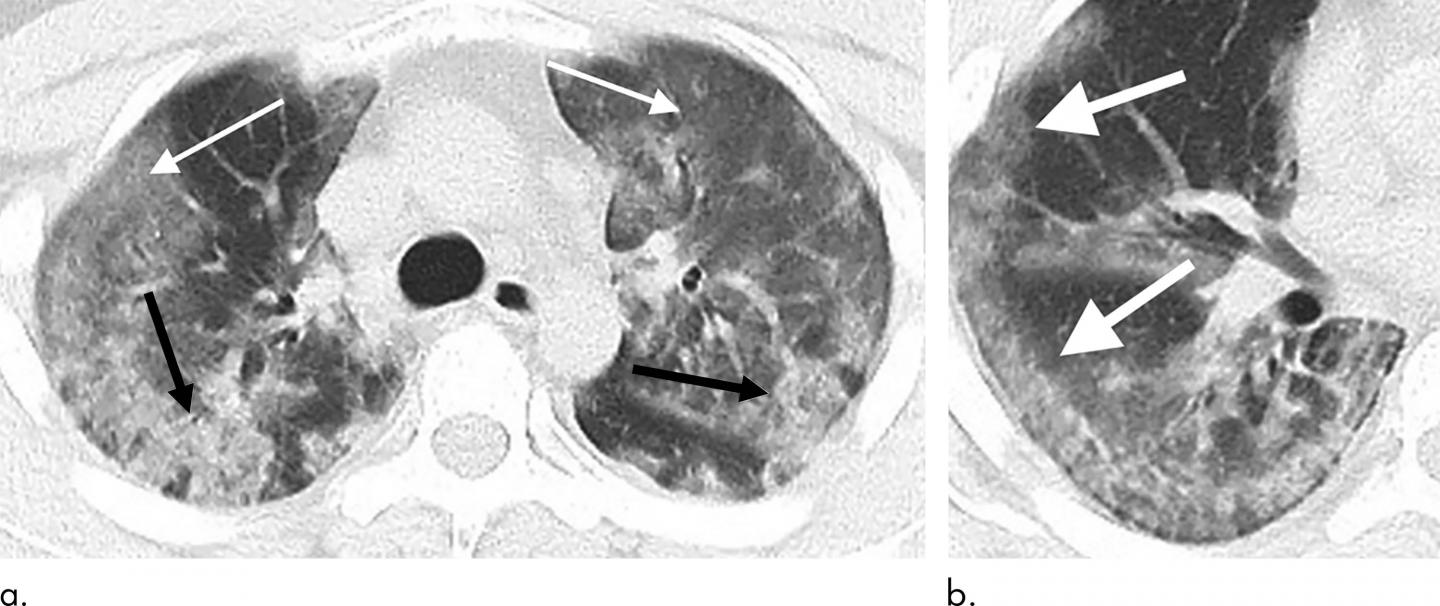

image: 29-year old male with unknown exposure history, presenting with fever and cough, ultimately requiring intensive care unit admission. (a) Axial thin-section non-contrast CT scan shows diffuse bilateral confluent and patchy ground-glass (solid arrows) and consolidative (dashed arrows) pulmonary opacities. (b) The disease in the right middle and lower lobes has a striking peripheral distribution (arrow).

The analysis showed that 2019-nCoV typically manifests on CT with bilateral ground-glass and consolidative pulmonary opacities. Nodular opacities, crazy-paving pattern, and a peripheral distribution of disease may be additional features helpful in early diagnosis. The researchers also noted that lung cavitation, discrete pulmonary nodules, pleural effusions and lymphadenopathy are characteristically absent in cases of 2019-nCoV.